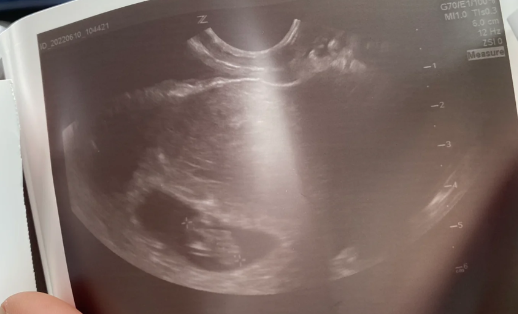

胎儿性别测试杯是2006年美国科学家研制的,检测原理是通过分离人体内激素与专门的化学物质接触后发生的反应来进行,将孕妇尿液装入杯中后的有没有变色来进行男女辨别。

美国胎儿测试杯使用简单,结果也比较好看,盛入尿液10分钟后,可以观察测试杯中的颜色变化,绿色为男孩,橙色为女孩。